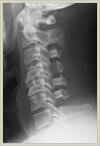

頚椎は7つの椎骨で構成されており、椎骨の後方には腰椎と同じく脊柱管という神経の通り道が存在します。頸椎の場合は腰椎と異なり、脊柱管の中を通っている神経は脊髄と呼ばれ、脳と同じ中枢神経です。このため、腰椎と同様の圧迫性病変でも異なった症状を呈します。頚椎症性脊髄症とは頚の椎骨(頚椎)に加齢性変化が生じ(頚椎症)、これにより脊髄の症状(脊髄症)を生ずるという意味です。頚椎椎間板ヘルニアは腰椎椎間板ヘルニアと同じ病態ですが、症状が頸椎部と腰椎部では違ってきます。頚椎部の場合は椎間板ヘルニアの場所によっても違いますが、頚から上肢にかけての放散痛(電気が走るような痛み)が典型的で、これは頚を動かすと増強します。また中心部に突出すると頚椎症性脊髄症と同じく脊髄の症状を呈します。脊髄の症状というのは具体的には、手の細かな運動が困難(お箸が持ちにくい、字が書きにくい、ボタンがはめにくい等)になったり、脚が突っ張って歩きにくい、階段を下りるとき足ががくがくする、上肢の筋萎縮、脱力、上下肢および体幹のしびれなど、全身に症状が出現します。頚椎椎間板ヘルニアの放散痛であれば、保存的加療(投薬、安静、リハビリテーション、注射など)で症状が軽減する場合が多いですが、脊髄の症状の場合は徐々に進行する場合が多く、症状の程度により手術が必要になる場合もあります。手術は後方法と前方法の2種類がありますが、それぞれ一長一短があり、画像所見や臨床症状によってどちらを選択するか決めています。 1ヶ所の頚椎椎間板ヘルニアで後方から摘出可能なケースでは、腰椎椎間板ヘルニアと同じく、直径18ミリの内視鏡チューブを用いて手術を行っており、2センチの傷ですみ、入院期間も約7日間となります。

頚椎後縦靱帯とは頚椎骨の後方に存在し上下の椎骨と連続している靱帯で脊髄から見ると前方に存在します。頚椎後縦靱帯骨化症とは本来の柔らかい靱帯が骨に置き換わって、徐々に厚さを増し、脊髄を圧迫するという病気です。症状は頚椎症性脊髄症と同じく脊髄の症状が主ですが、この後縦靱帯の骨化は徐々に起こるため症状が出現しにくく、非常に高度に脊髄が圧迫されて、初めて症状が出現する場合があります。症状が軽度な場合には、保存的加療(投薬、安静、リハビリテーションなど)で経過観察していますが、症状が進行性の場合には手術加療の適応となります。当センターでは病巣範囲に応じて前方法か後方法を選択してします。病巣範囲が少なければ、前方法で手術用顕微鏡下に骨化靱帯を摘出する方法を選択し、その存在、範囲が広ければ後方法を選択しています。厚生労働省の特定疾患として認められており、医療費の公費負担を受けることができる場合があります。